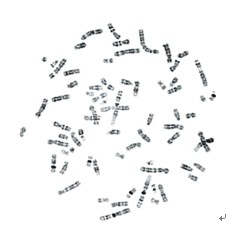

BandView染色體條帶分析系統(tǒng)

型號(hào):BandView

詢價(jià):400-0630-558

廣州市深華提供的 BandView染色體條帶分析系統(tǒng) 質(zhì)量過硬,物美價(jià)廉。如需服務(wù)請(qǐng)點(diǎn)擊右側(cè)在線客服,也可以直接致電我們,400-0630-558,18819137158,我們將會(huì)竭誠(chéng)為您服務(wù)!